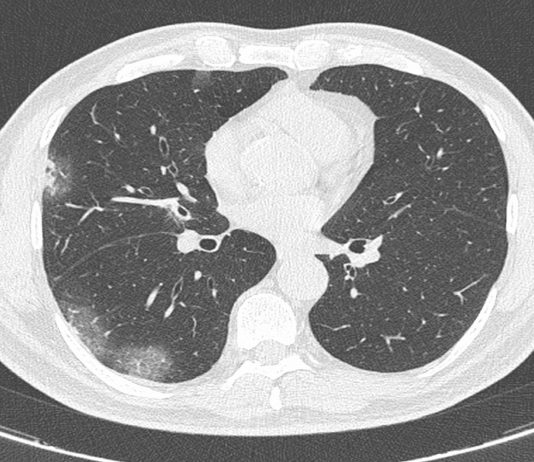

Uomo di 60 anni

Comparsa di dispnea e ipertermia